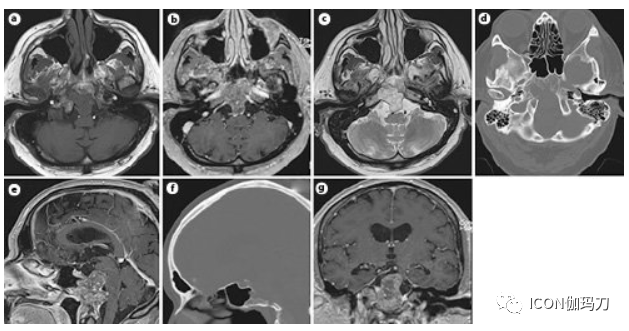

图2.颅内脊索瘤的MRI和CT扫描。轴位(a-c)、矢状位(e)、和冠状位(g) T1加权和轴位T2加权(c) MRI显示肿瘤向斜坡/斜坡后延伸。b, e, g对比增强图像。轴位(d)和矢状位(f) CT扫描显示斜坡受累。